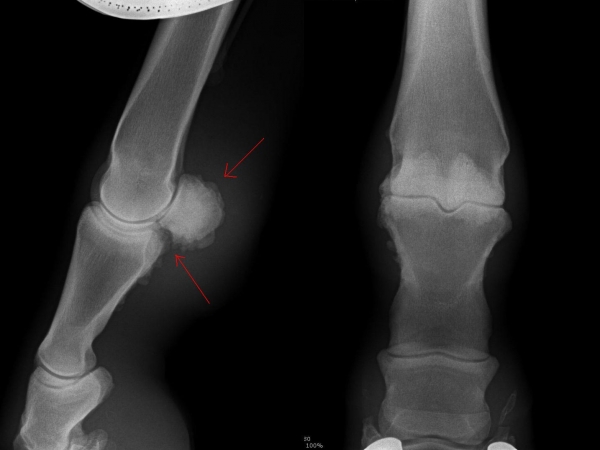

Fragment na spěnkové kosti